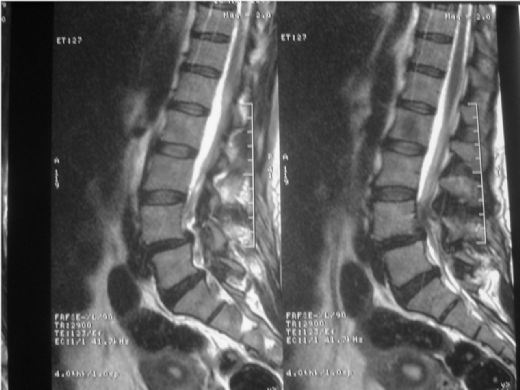

Bel fıtığı, omurgadaki disklerin kayması sonucu oluşan bir durumdur ve ciddi rahatsızlıklara yol açabilir. Manyetik Rezonans Görüntüleme (MR), bu durumu tanımlamak için etkili bir yöntemdir. MR, disk değişikliklerini, sinir kökü kompresyonunu ve inflamasyonu net bir şekilde gösterir, böylece uygun tedavi seçenekleri belirlenebilir.

Bel Fıtığı MR ÖzellikleriBel fıtığı, tıbbi literatürde "lumbar disk hernisi" olarak adlandırılan bir durumdur ve omurganın alt kısmında bulunan intervertebral disklerin, çevresindeki dokulara doğru kayması sonucu meydana gelir. Bu durum, genellikle bel ağrısı ve bacaklarda sinir kökü irritasyonuna bağlı olarak çeşitli semptomlarla kendini gösterir. Manyetik Rezonans Görüntüleme (MR), bel fıtığının tanı ve değerlendirilmesinde yaygın olarak kullanılan bir görüntüleme yöntemidir. Bel Fıtığı Nedir? Bel fıtığı, bel bölgesindeki disklerin, normal anatomik yerlerinden kayarak sinir köklerine baskı yapması sonucunda oluşan bir durumdur. Bu durum, genellikle şu şekillerde ortaya çıkabilir:

Bu durumlar, belde ağrı, bacaklarda uyuşma, karıncalanma ve güçsüzlük gibi çeşitli semptomlara yol açabilir. MR Görüntüleme Yöntemi Manyetik Rezonans Görüntüleme (MR), vücut içindeki dokuların ayrıntılı görüntülerini elde etmek için manyetik alanlar ve radyo dalgaları kullanan non-invaziv bir görüntüleme tekniğidir. MR, yumuşak dokuların görüntülenmesinde X-ışınlarına göre daha üstün sonuçlar verir. Bel fıtığı gibi durumların tanısında oldukça etkili bir yöntemdir. Bel Fıtığı MR Özellikleri Bel fıtığı MR görüntülerinde dikkate alınması gereken bazı önemli özellikler şunlardır:

MR Raporu ve Değerlendirme MR raporları, bel fıtığının ciddiyetini ve tedavi seçeneklerini belirlemek için kritik öneme sahiptir. Rapor, fıtığın boyutunu, konumunu ve çevresindeki yapılar üzerindeki etkisini içermelidir. Bu değerlendirme, cerrahi veya konservatif tedavi yöntemlerinin planlanmasında yardımcı olur. Sonuç Bel fıtığı, birçok bireyi etkileyen yaygın bir sağlık sorunudur ve MR görüntüleme, bu durumun tanı ve değerlendirilmesinde oldukça önemli bir rol oynamaktadır. Bel fıtığı MR özellikleri, tanı sürecinde doktorlara yardımcı olurken, doğru tedavi yöntemlerinin belirlenmesinde de kritik bir öneme sahiptir. Bu nedenle, bel fıtığı şikayetleri olan bireylerin, uzman bir hekim tarafından değerlendirilmesi ve gerekirse MR çekimi yapılması önerilmektedir. Ek olarak, bel fıtığı tedavisinde fizik tedavi, ilaç tedavisi ve gerektiğinde cerrahi müdahale gibi çeşitli seçenekler bulunmaktadır. Tedavi sürecinin bireye özel olarak planlanması, iyileşme sürecini hızlandıracak ve yaşam kalitesini artıracaktır. |